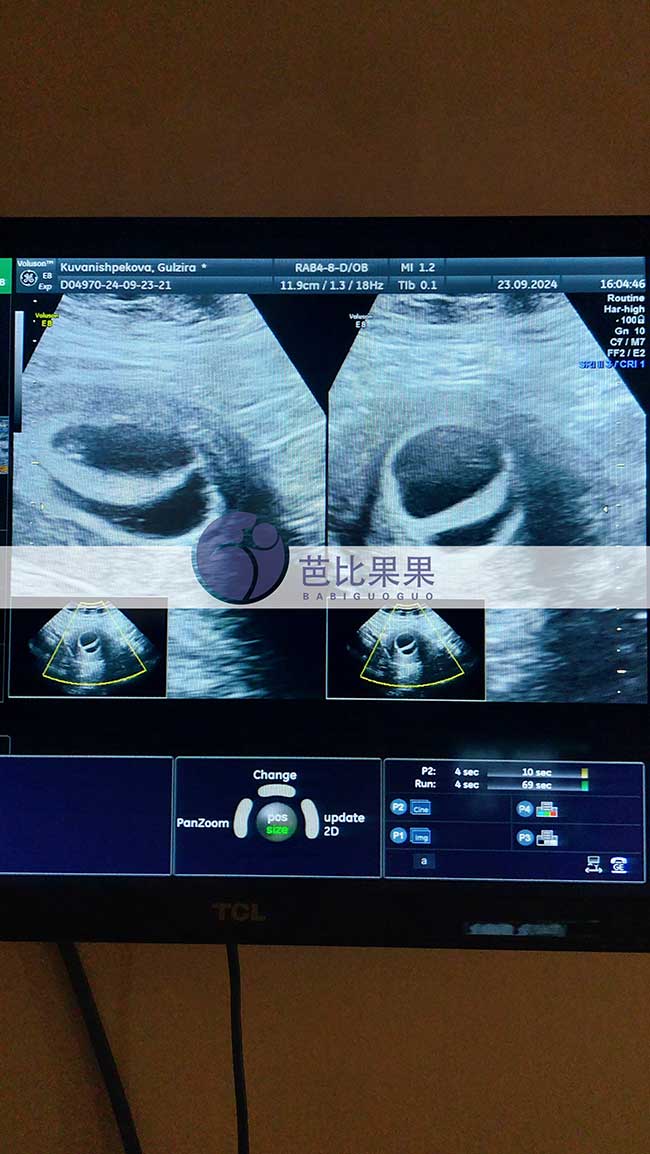

浙江Y女士在格鲁吉亚助孕匹配的试管妈妈做孕7周+B超

浙江Y女士在格鲁吉亚助孕匹配的试管妈妈做孕7周+B超,双胞胎都发育出胎心啦